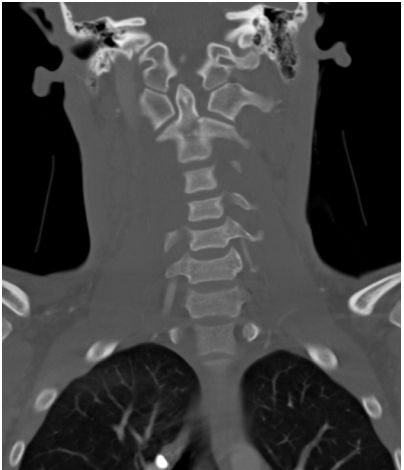

What’s the Diagnosis? Gepost op 20 maart 201820 maart 2018 door netwerkvsseh What’s the Diagnosis? @emdaily.cooperhealth.org Dit delen: Delen op X (Opent in een nieuw venster) X Share op Facebook (Opent in een nieuw venster) Facebook Delen op LinkedIn (Opent in een nieuw venster) LinkedIn E-mail een link naar een vriend (Opent in een nieuw venster) E-mail Afdrukken (Opent in een nieuw venster) Print Vind-ik-leuk Aan het laden... Gerelateerd